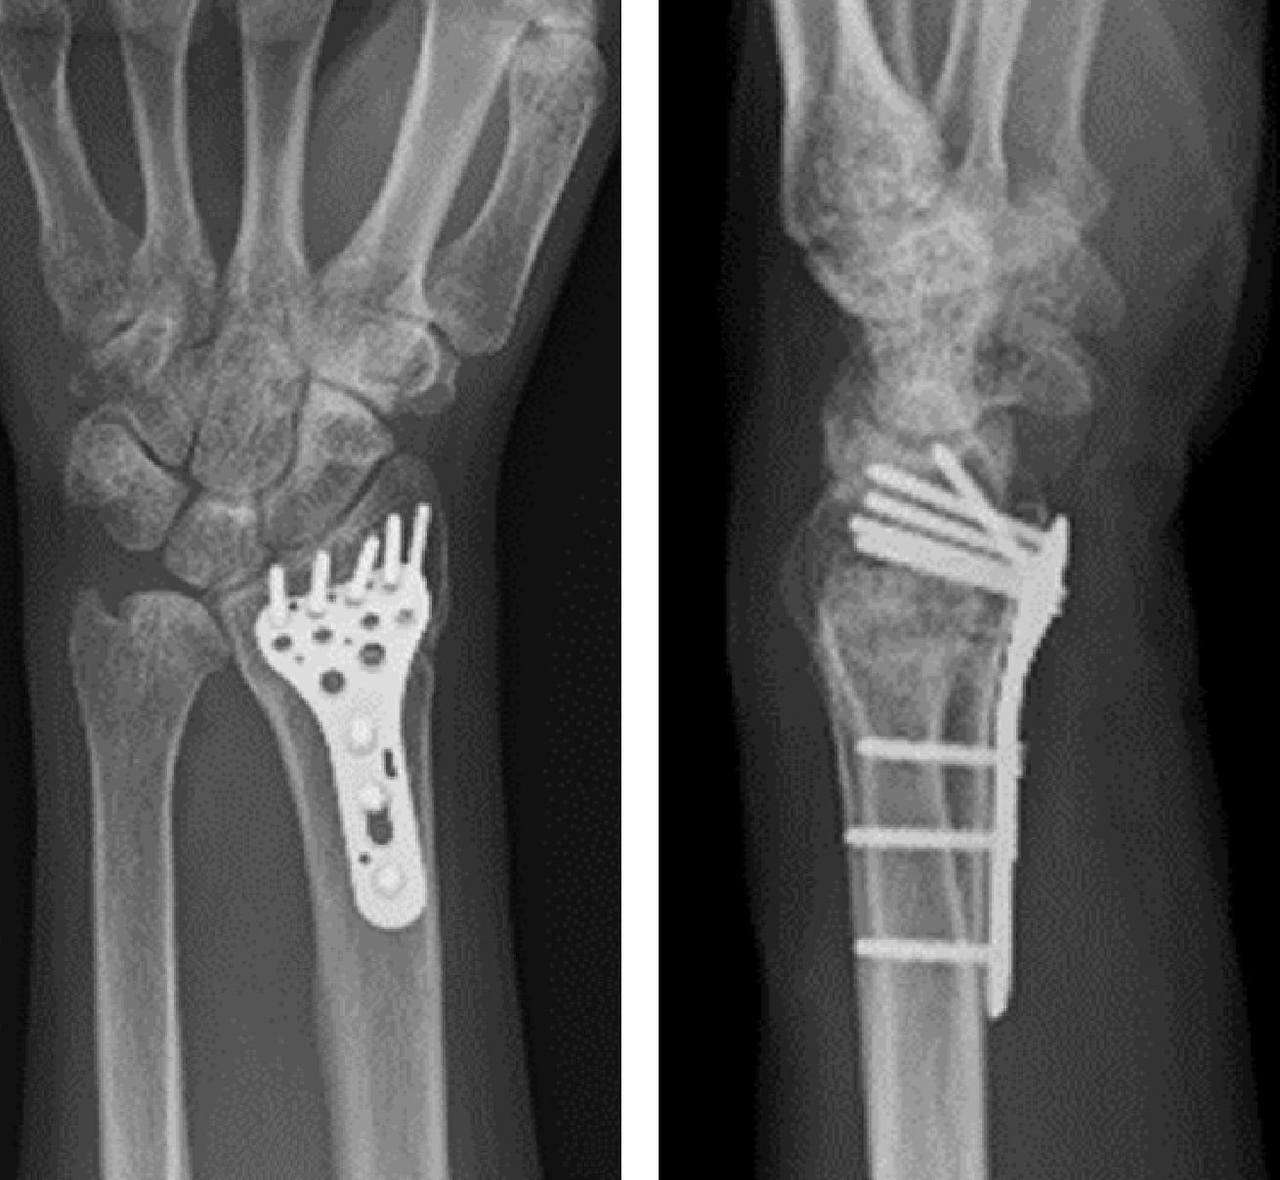

- 분쇄·불안정 골절

- 고에너지 충격(추락·교통사고)에서 발생, 골편이 여러 조각.

- 수술적 고정(금속판·나사) 후 재활 필요.

수술적 치료

- 볼라(locking) 플레이트 고정

- 조기 관절 가동 범위 운동(ROM)이 가능.